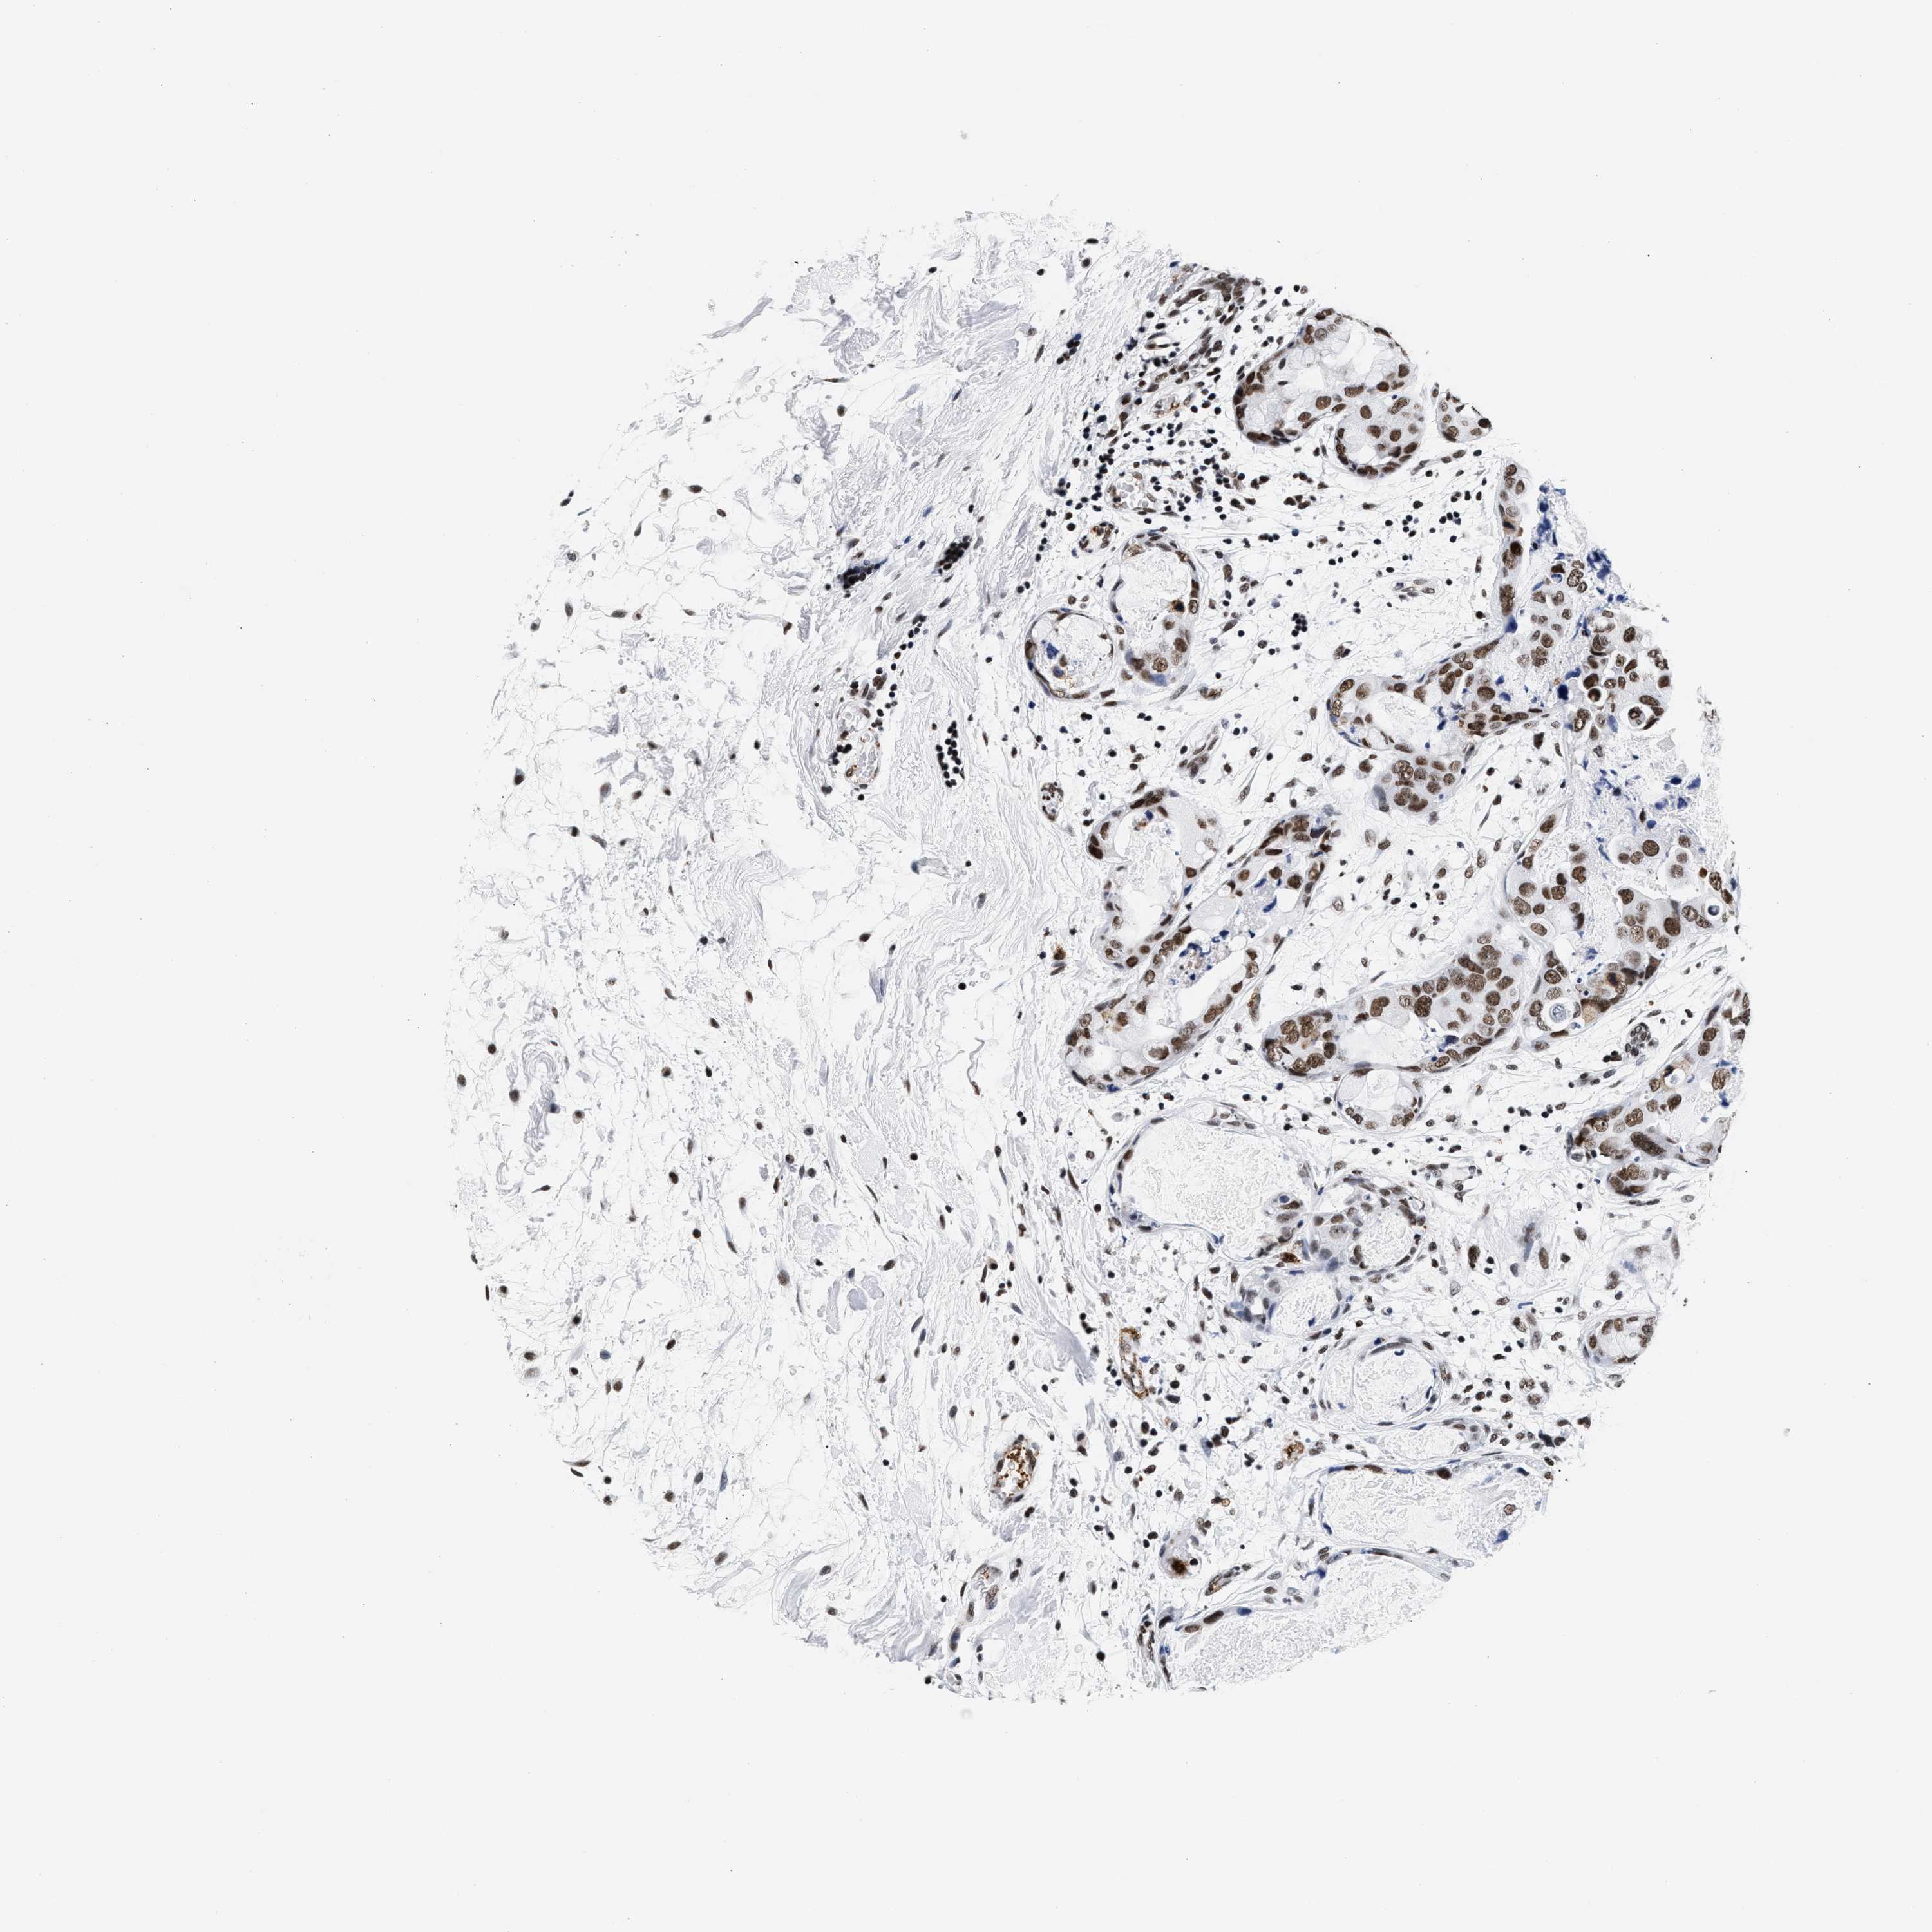

CANCER BREAST CANCER Show tissue menu

BRCA TCGA BRCA VALIDATION PROTEIN EXPRESSION